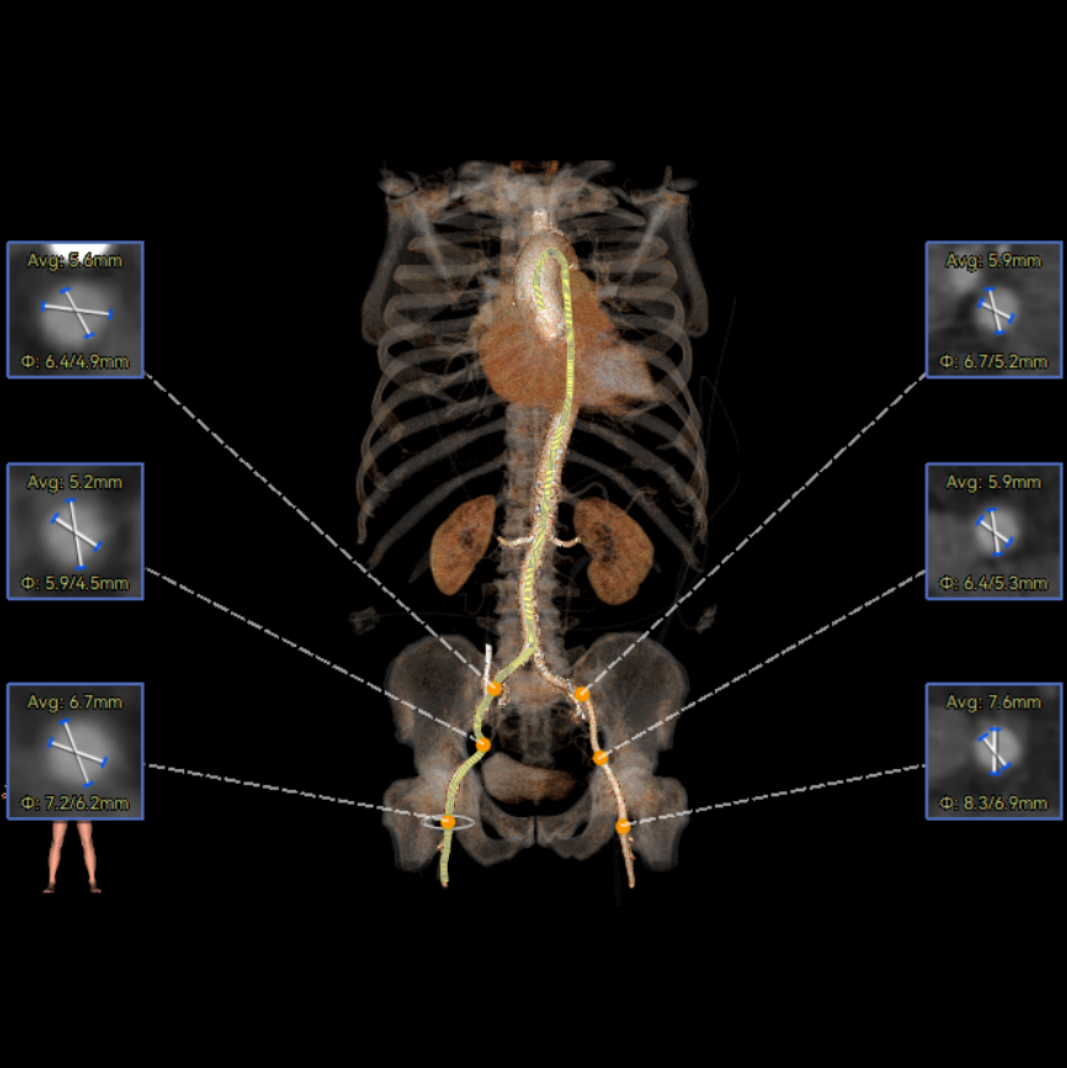

患者病史 术前超声提示:主动脉瓣退行性病变;中-重度狭窄并轻度返流;中-重度三尖瓣返流;中度肺高压 术前CT 三叶瓣,瓣叶增厚轻度钙化,右无交界有粘连,预计可以扩开,主动脉根部直径23.7mm,LVOT直径24.3mm,呈直筒型;双侧冠脉开口高度可,瓣叶长度小于冠脉开口上缘到主动脉根部的距离;窦部空间可,STJ、升主动脉内径可;主动脉水平夹角43.6°,非横位心;主动脉弓角、弓距可,左室内径可;外周入路无明显迂曲,有零星散状钙化,双侧股动脉内径可,均能通过20F大鞘,右股低分叉。 手术策略 推荐右侧股动脉为主入路使用20F大鞘,左侧股动脉为辅入路,右股分叉上方1cm穿刺;推荐使用22mm球囊预扩,预装AV26瓣膜,备AV29瓣膜,初始定位为真实瓣环上方3mm,瓣膜释放过程中释放张力使其自然下滑,工作位观察瓣膜稳定性,最终理想位置为零位;左右重合位:RAO23°CAU32°;右窦居中位:LAO5°CAU12°;左冠切线位:LAO34°CRA14°。 手术过程 术中右股动脉痉挛,内径变为3.8mm,遂更换左腋动脉入路;18球囊预扩,后植入AV26 ProStyle A®瓣膜;瓣膜精准释放于目标位置,超声显示无明显瓣周漏,血流动力学即刻改善。 术中右股动脉痉挛,内径变为3.8mm,更换左腋动脉 主动脉根部造影 18球囊预扩 初始定位 工作位观察 术后即刻表现:无瓣周漏,术后峰值压差10mmHg 术后3天复查超声峰值压差14mmHg Prostyle A®预装干瓣——助力临床最优化解决方案: 轻松过弓,精准可控:该病例经左腋动脉入路,输送系统较细的尺寸+柔顺的输送系统通过性能得到了很好的验证; 释放稳定:平衡的径向支撑力降低了释放过程中的张力,流入端小锥角设计能够迅速锚定贴边,80%可回收使得观察位和释放后的位置差距减少,大大提高了释放过程中的精准性,能够轻松应对高难度病例; 预装干瓣 便捷顺安:金仕生物专利抗钙化技术运用纳米技术去除组织内的细胞碎片和磷脂,封闭游离醛基,从根本上阻断了瓣膜钙化的多项因素,显著提升了瓣膜的耐久性;同时,相比较传统戊二醛保存方式,干式存储最大限度的保留心包的亲水亲油平衡,还原组织天然曲柔性,进一步保障了瓣叶开合,保证长期耐久性; 谢年谨教授 广东省人民医院 谢年谨教授指出:“对于外周血管条件较差的心脏瓣膜病患者,腋动脉路径凭借其更直接的解剖通路与更稳定的输送环境,为手术安全提供了重要保障,尤其适用于股动脉入路失败的复杂病例。该路径不仅能显著降低血管损伤、出血等并发症风险,还能通过更清晰的操作视野提升手术成功率;尤其在高龄、动脉硬化严重的患者群体中,腋动脉路径的适应性优势更为突出。 专家简介 荆志成 广东省人民医院 谢年谨 广东省人民医院 刘勇 广东省人民医院 · END ·